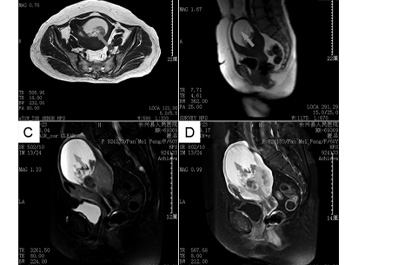

这项研究报告了1例59岁绝经后女性患子宫骨肉瘤并表现为恶性混合苗勒管肿瘤的罕见病例。通过MRI、超声检查、血清肿瘤标志物检测、手术及病理诊断等方式,对患者病情进行详细分析,并探讨了该疾病的相关特征和治疗方案。

结果发现,患者经手术和病理诊断,确诊为子宫骨肉瘤合并恶性混合苗勒管肿瘤,包含子宫内膜腺癌、软组织肉瘤和骨肉瘤成分,且存在淋巴结转移,分期为IIIC2期。